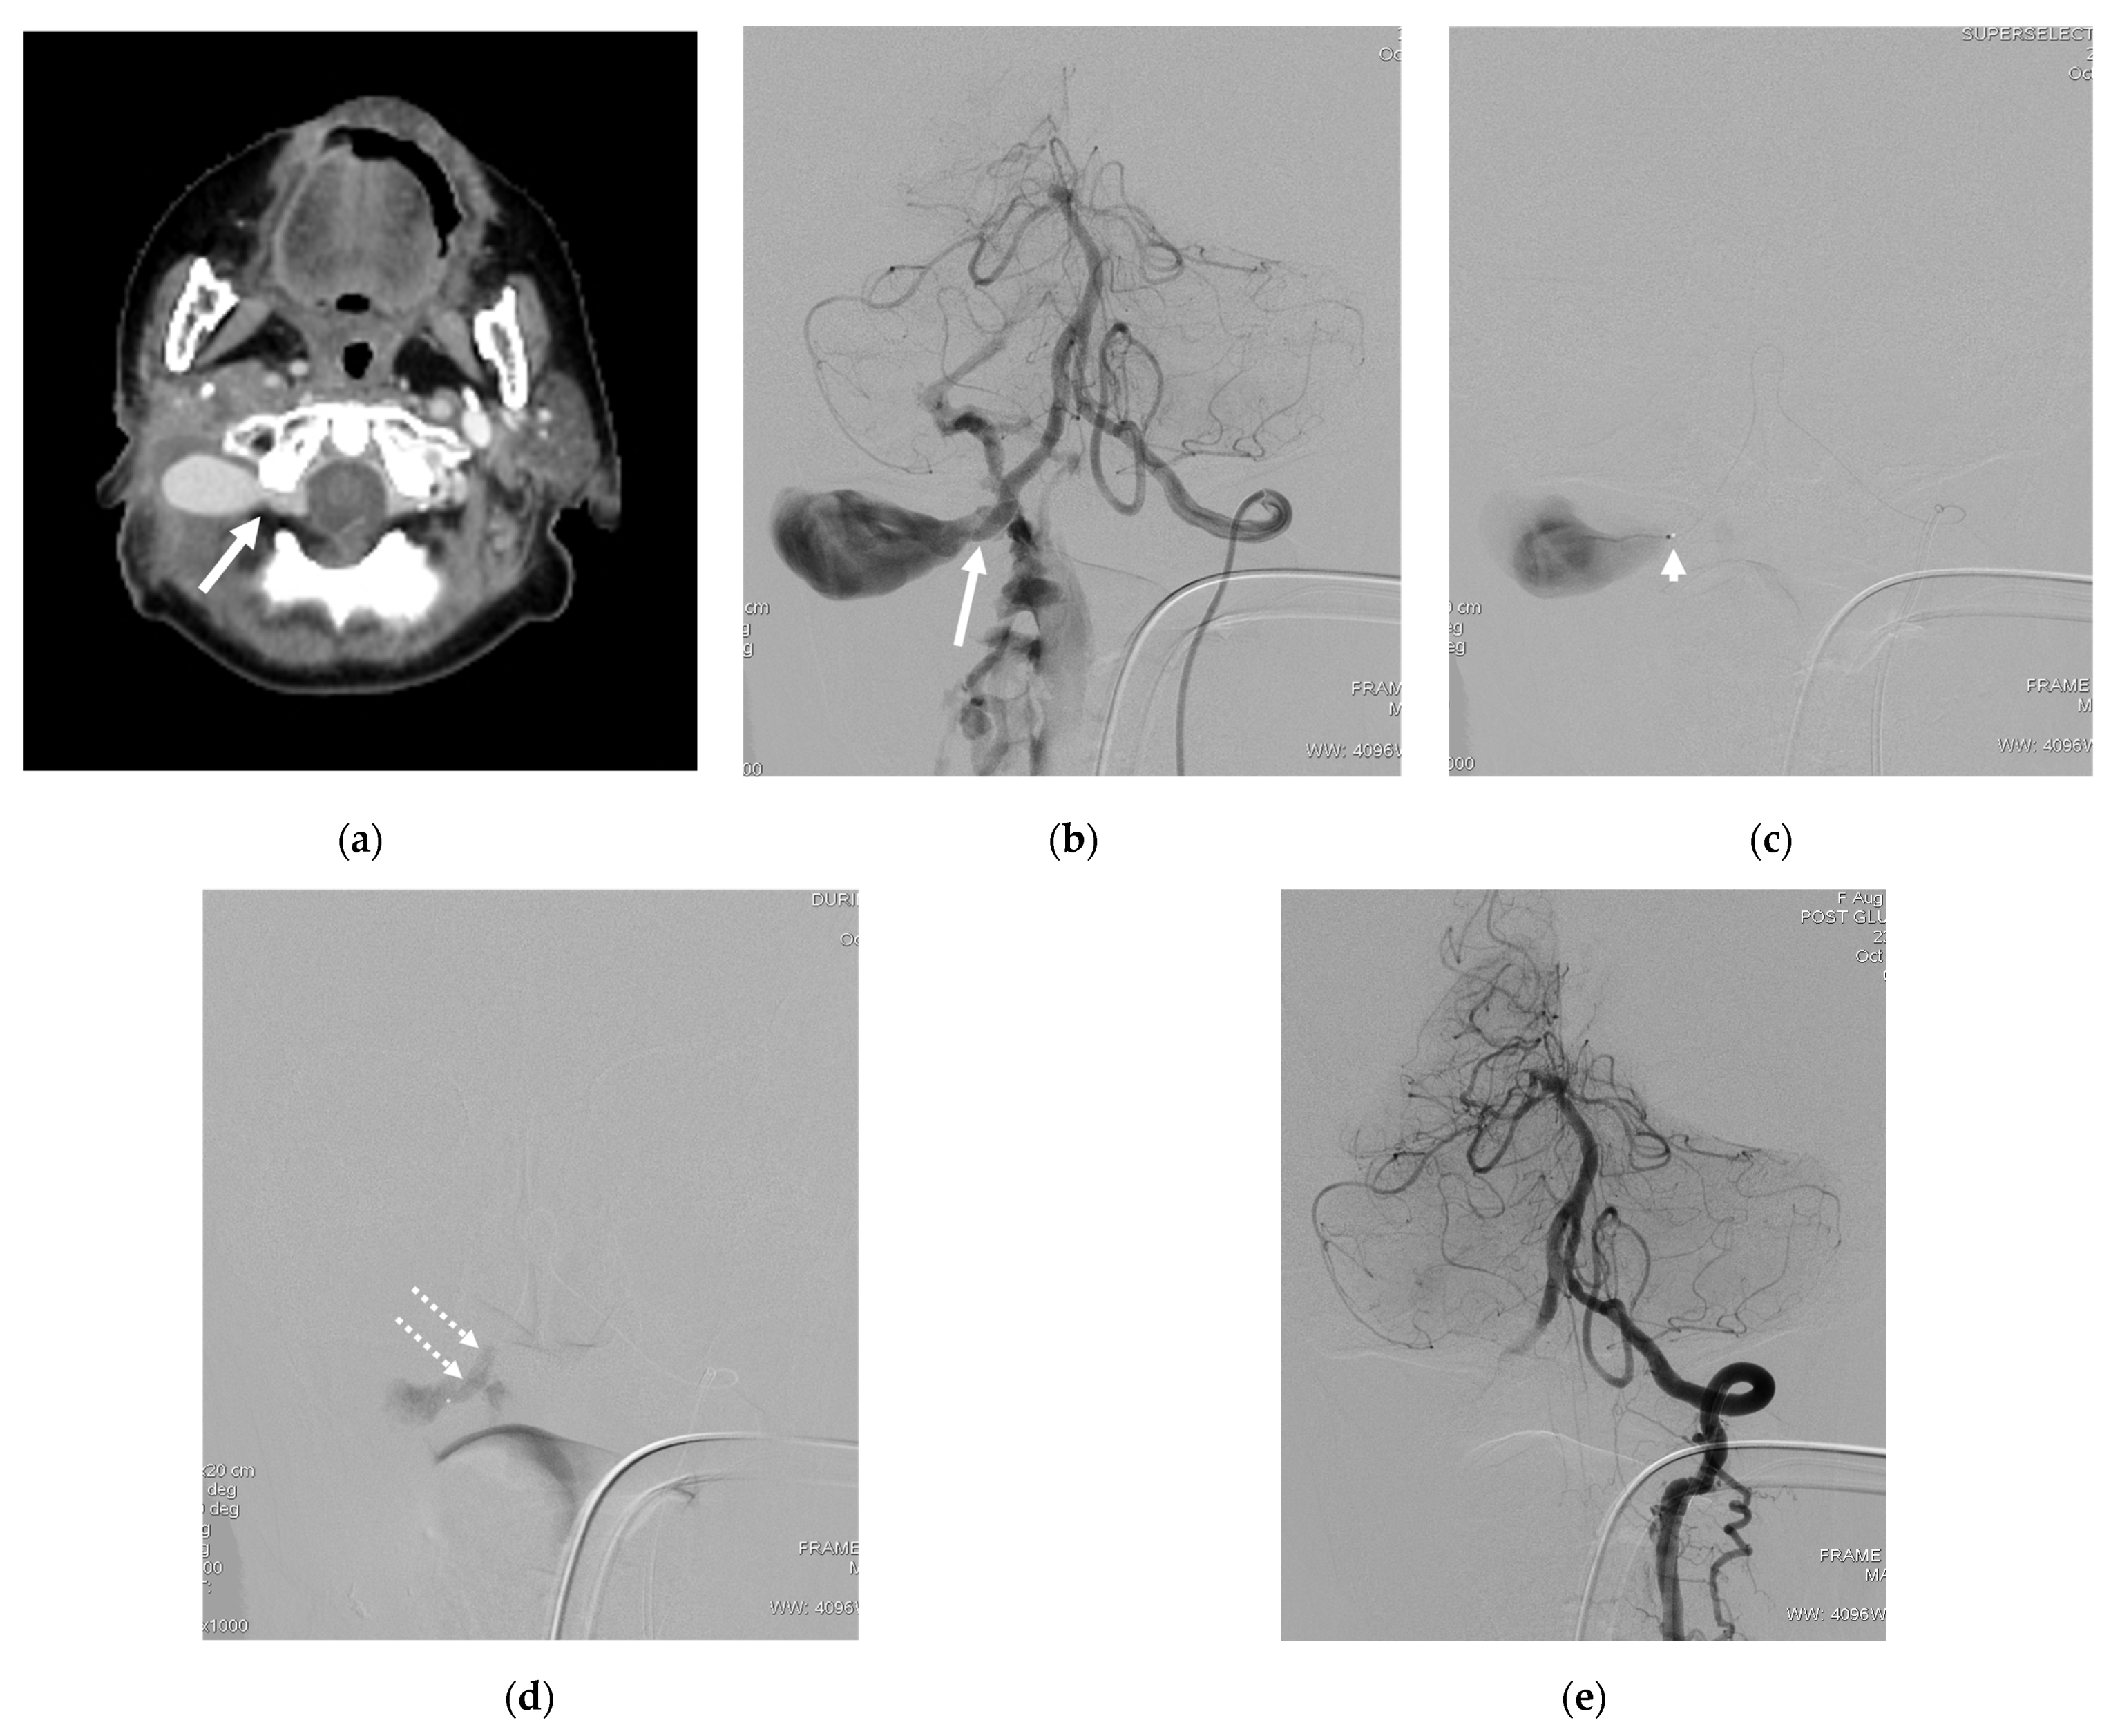

| 1 | F | 49 | Neck mass; tinnitus; right arm weakness | Unknown | S | Radicular vein; VVP with venous pouch | Y | C and NBCA | O | Improved | Transient occipital pain |

| 2 | F | 33 | Bleeding | Central line injury | T | VVP | N | C | O | Improved | None |